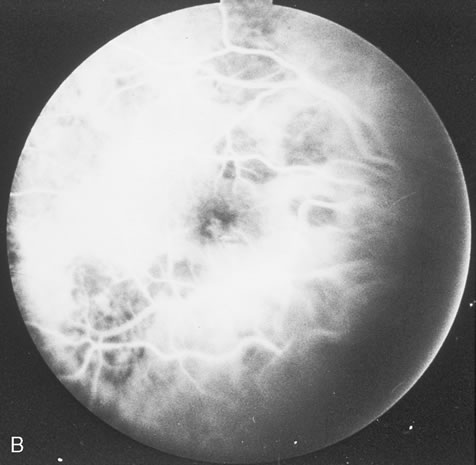

The acute retinal necrosis (ARN) syndrome is most often caused by the herpes zoster virus, although occasionally it may be a result of herpes simplex infection.12 It is typically described in healthy patients although association with immunosuppressed patients has also been described. Granular, nonhemorrhagic areas of retinal necrosis may be observed in the fundus, often rapidly coalescing with resulting blindness often caused by retinal detachment. There is often an associated vasculitis and vitritis. In immunocompromised patients VZV or HSV retinitis may also take the pattern of progressive outer retinal necrosis (PORN) (Fig. 6). PORN differs from ARN in that the former is multifocal, localized to the outer retina, and is less often associated with vasculitis and vitritis.

Pneumocystis carinii pneumonia once was the most common presentation of AIDS. It is typically of insidious onset, with features including dry cough, dyspnea, and a diffuse bilateral interstitial infiltrate evident on a chest roentgenogram. Typical multifocal fundus lesions have been described. They are yellow-white and have a characteristic pattern on fluorescein angiography (Fig. 10A, 10B, and 10C). Diagnosis is made by demonstrating the protozoon via sputum induction, bronchioalveolar lavage, and transbronchial or open-lung biopsies. Treatment modalities include trimethoprim-sulfamethoxazole (TMP-SMX).31